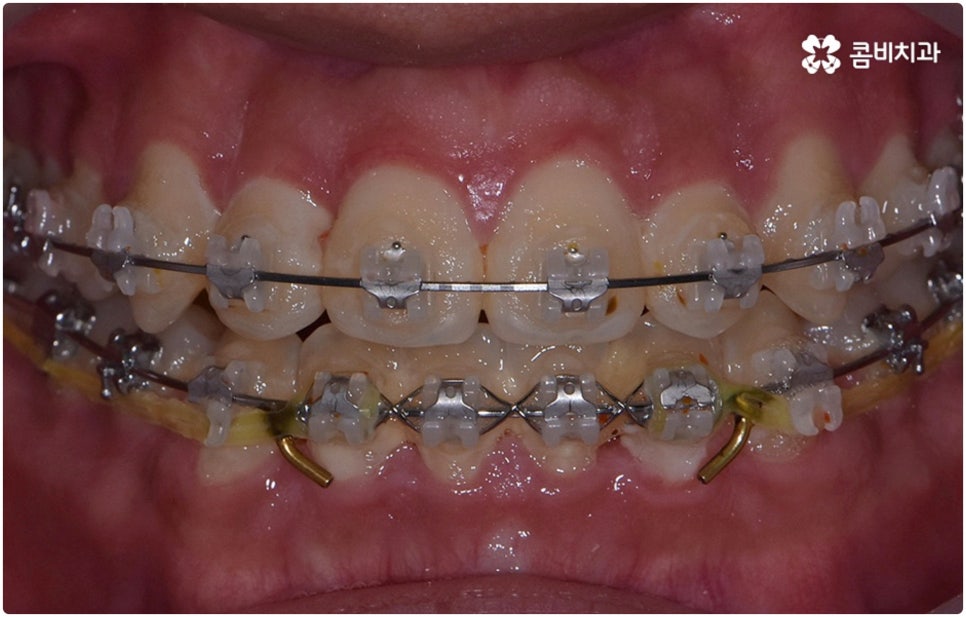

부정교합은 부정교합 1급, 부정교합 2급, 부정교합 3급 이렇게 세가지 종류로 나눌 수 있는데요. 부정교합 1급은 이를 다물었을 때 위아래 어금니는 잘 맞물리지만 덧니가 있거나 치아 사이가 살짝 벌어져 있는 경우처럼 치열이 삐뚤어진 경우를 말하는 것으로 골격이나 구조적인 부분에는 크게 문제가 없기 때문에 정도가 심하지 않다면 보다 빠르고 간편한 교정 치료가 가능한 케이스라고 할 수 있어요. 부정교합 2급은 상악이 하악보다 더 튀어나온 상태로 위에서 언급했던 무턱, 돌출입이 여기에 속하며 반대로 부정교합 3급 은 주걱턱처럼 하악이 상악보다 튀어나온 상태를 의미하고 있습니다.

환자분들마다 상황은 모두 다르기 때문에 부정교합 교정 치료를 할 때는 정밀 검진 후 맞춤 치료 계획에 따라 무리하지 않게 진행하는 것이 중요한 포인트라고 할 수 있어요. 이때 구강내 상태 (치아, 잇몸, 치열, 교합 등) 뿐 아니라 구강 외 상태 (뼈의 위치 및 구조 발달, 얼굴 정면과 측면 등 안모 비율) 와 같은 모든 부분을 꼼꼼하게 촬영하고 환자의 연령 및 생활 습관 등을 종합적으로 고려하여 원인을 분석한 다음 치아를 어떻게 얼마나 움직여야할지 면밀하게 교정 플랜을 세우는 것이 필요하므로 3D CT, 모르페우스 같은 정밀 진단 기계를 갖추고 있는 치과에서 다양한 임상 경험을 통해 뛰어난 기술력을 가지고 있는 담당의 선생님께 치료 받으시길 권유드리고 있습니다.

부정교합 2급, 부정교합 3급 과 같이 구조적인 부분에 원인이 있는 문제라면 잇몸뼈가 다 굳고 난 다음인 중장년 성인분들의 경우 교정 치료를 받는 것이 과연 부정교합 개선에 효과가 있을까 궁금해 하실 수 있어요. 특히 턱관절 이상 문제는 수술을 통해서만 고칠 수 있다고 알고 계셨던 분들은 부담을 느끼고 치료를 미루셨을 수 있는데요. 물론 성인분들의 경우 상황에 따라, 예를 들어 정도가 매우 심한 부정교합 3급 케이스라면 악교정수술을 받아야 할 수도 있습니다. 또한 대부분의 부정교합 2급, 부정교합 3급 케이스들 같은 경우 초등학교 고학년에서 중학교 저학년 사이에 교정 치료를 시작하는 것이 좋다고 권유하는 것도 사실인데요, 그 이유는 아무래도 치아 이동 속도가 빠르고 전반적인 발달 상황에 맞추어 자연스럽게 치료를 진행할 수 있는 성장기의 특성상 이 시기부터 지속적으로 턱뼈 크기 부조화를 조절하고 상하악의 올바른 성장을 유도하는 게 보다 효율적이기 때문이라고 할 수 있어요.

하지만 관련 기술 발달로 교정에 있어서 적기라는 것이 크게 의미가 없어진 근래에는 정도가 많이 심각하지 않다면 중장년 성인분들의 경우에도 각자에게 맞는 교정 치료를 통해서 얼마든지 부정교합 개선이 가능하니 안될 것이라고 지레 짐작을 하여 내원을 망설이시기 보다는 먼저 교정 치료를 위한 검진을 받아보고 자신의 상황에 대해서 숙련된 의료진과 충분히 상담해 보시길 권유드리고 있습니다. 특히 수술적인 치료를 할 때도 교합을 바로잡기 위해서는 치과와 협진하여 진행하는 케이스가 많으니 교정을 통한 부정교합 개선 및 턱관절 치료 효과에 대해 크게 의구심을 가지실 필요는 없을 거예요. 상황에 따라 교정 치료만으로도 기능적 개선은 물론 균형잡힌 안모와 호감가는 인상으로의 변화가 가능한 경우가 많으니 불편함을 참고 계시지 말고 정밀 진단과 상담부터 차근차근 시작해 보시면 필요한 도움을 받아 보실 수 있어요.